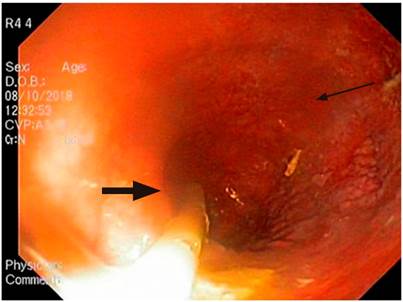

During the esophagogastroduodenoscopy, traces of food content were found in the esophagus. The esophageal body was severely dilated, tortuous, with angulations, and the gastroesophageal junction was punctiform, although it was difficult to pass through (Figure 3). Barium esophagogram revealed a severely dilated esophageal body, with the lower esophagus in a sigmoid-likepattern (Figure 4).

Figure 3 Esophagogastroduodenoscopy (upper GI endoscopy or EGD). Proximal esophagus with increased luminal caliber, nasogastric tube and undigested food remains (thick arrow). Congested mucosa with no stigmata of recent hemorrhage (thin arrow). Source: Gastroenterology Unit. Hospital Universitario San Ignacio. Bogotá D.C. Colombia.